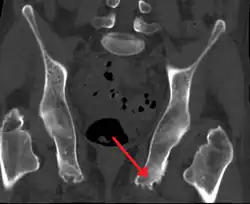

| Enthesopathy of the pelvis likely due to ankylosing spondylitis | |